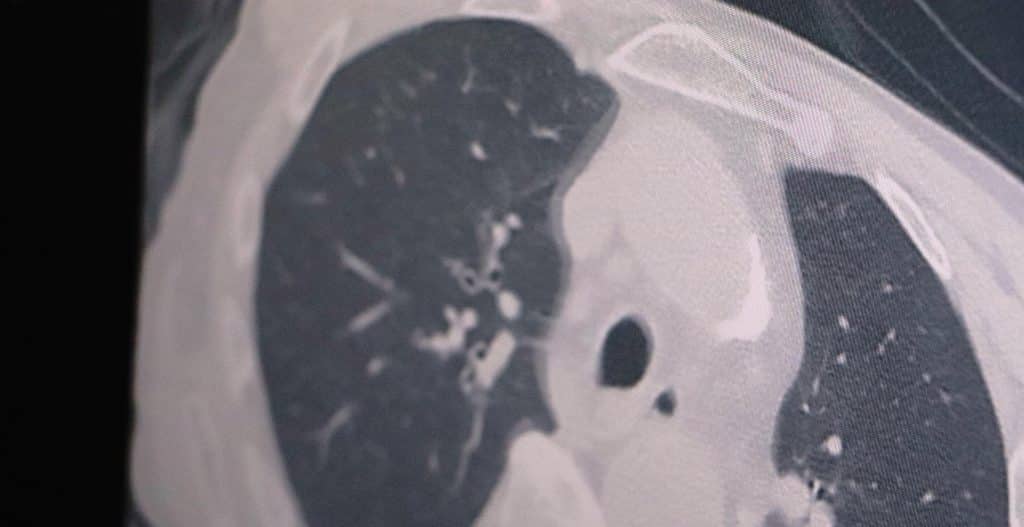

Yoğun bakımlarda yatan hastaların büyük bir çoğunluğu genel durumu düşkün olup da tesadüf pozitif gelen hastalardır. Yoksa aşılarını tam olan kişilerde hala akciğer tutulumu gözlenmiyor. Olduğunuz aşıların hala omicron varyantında akciğere inmesini önlediğini görüyoruz” dedi.

Kovidin seyri aşıların etkili olduğunu gösteriyor. Aşı etkisinden kaçan yeni mutasyonlar olursa akciğer tutulumları ve yoğun bakım yatışlarının olacağını beklediklerini ifade eden Özkaya, “Şu an için mevcut aşıların hala etkili olduğunu görüyoruz. Çünkü yoğun bakımda ve servislerde yatan hastalarda ciddi akciğer tutulumunun olmadığını görüyoruz. Özellikle hacdan dönen vatandaşlarımız hacda karşılaştıkları orta doğu virüsleriyle ilgili etkileşim içinde oldukları için bu vatandaşlarımızda mutasyon olma ihtimali var. O yüzden hacdan gelenleri karşılarken mümkün olduğunca mesafe kurallarına dikkat edeceğiz” diye konuştu.